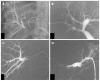

Hilar cholangiocarcinoma is a common malignant tumor of the biliary tree. It has poor prognosis with very low 5-year survival rates. Various imaging modalities are available for detection and staging of the hilar cholangiocarcinoma. Although ultrasonography is the initial investigation of choice, imaging with contrast enhanced computed tomography scan or magnetic resonance imaging is needed prior to management. Surgery is curative wherever possible. Radiological interventions play a role in operable patients in the form of biliary drainage and/or portal vein embolization. In inoperable cases, palliative interventions include biliary drainage, biliary stenting and intra-biliary palliative treatment techniques. Complete knowledge of application of various imaging modalities available and about the possible radiological interventions is important for a radiologist to play a critical role in appropriate management of such patients.We review the various imaging techniques and appearances of hilar cholangiocarcinoma and the possible radiological interventions.